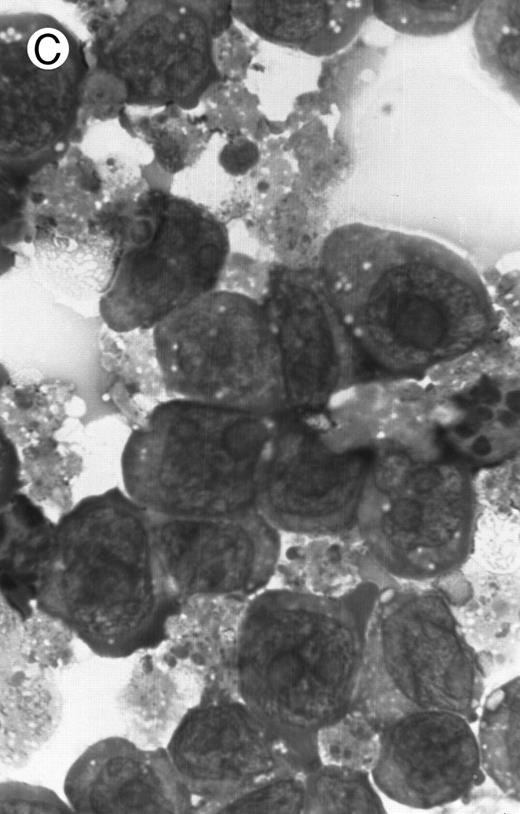

Morphology of PLB-985 cells (A) before treatment and after a 4-day treatment with (B) 1.25% DMSO (differentiation) or (C) 10−7 mol/L 9-cis-RA (apoptosis) (original magnification × 1,000).

We have shown above that activation of both RAR and RXR by 9-cis-RA or by the combination of selective ligands inhibits cell growth and induces cell death in PLB-985 cells. We wished to verify whether these retinoids also induced differentiation of PLB-985 cells before the onset of cell death. Microscopic examination of cell morphology after 4 days of treatment with 9-cis-RA demonstrated no differentiated phenotype (Fig 2C). On the other hand, DMSO-treated PLB-985 cells had a typical differentiated morphology (Fig 2B). We then examined alterations in several cell surface markers, especially those specific for differentiated granulocytes. We contrasted the known differentiation effects of retinoids on NB4 with PLB-985 cells. NB4 and PLB-985 cells express low levels of CD11b and no detectable CD11c, but high levels of CD13.2 44 As previously reported, treatment of NB4 cells with 9-cis-RA increases expression of CD11b and CD11c, and significantly reduces expression of CD13 (Fig 3, bottom), consistent with the differentiation of NB4 cells into granulocytes. Also consistent with their effects on cell growth, the RXR-selective ligand 100153 did not have any effect on the surface marker expression in NB4 cells, but the RAR-selective ligand 100272 induced the same differentiation-specific changes as 9-cis-RA. In PLB-985 cells, DMSO-induced granulocytic differentiation stimulates the surface expression of CD11b44 (and data not shown). In our experiments PLB-985 cells treated with 9-cis-RA did not show any increase in CD11b and CD11c levels. These cells also continued to express high levels of CD13, even at day 4, when the cell counts began to decrease (Fig 3, top). As expected, the selective ligands, either alone or in combination, also did not have any effect on the expression of these markers in PLB-985 cells. These results show that stimulation of both RAR and RXR inhibits growth and induces cell death without differentiation in PLB-985 cells.

Induction of apoptosis by 9-cis-RA. Microscopic observation of retinoid-treated PLB-985 cells showed typical characteristics of apoptosis, including cell shrinkage, membrane blebbing, and nuclear fragmentation (Fig 2C). Furthermore, apoptotic cells were observed as early as 2 days after the addition of retinoids, and increased in numbers with the progression of treatment (data not shown). A typical molecular characteristic of apoptosis is genomic DNA cleavage into internucleosomal segments attributed to the specific activation of an endogenous endonuclease.45 Several cell lines (MOLT-3, T-cell ALL; CEM, T-cell ALL; PLB-985; Raji, Burkitt lymphoma; HUT 78, cutaneous T-cell lymphoma) were treated for 4 days with 10−6 mol/L 9-cis-RA. DNA was isolated from these cultures, separated on an agarose gel, and visualized by ethidium bromide staining. Only RA-treated PLB-985 cells exhibited a typical apoptotic “DNA laddering” pattern (data not shown). Similar results were obtained after treatment with all-trans-RA and 13-cis-RA (data not shown); however, this effect was most pronounced with 9-cis-RA.